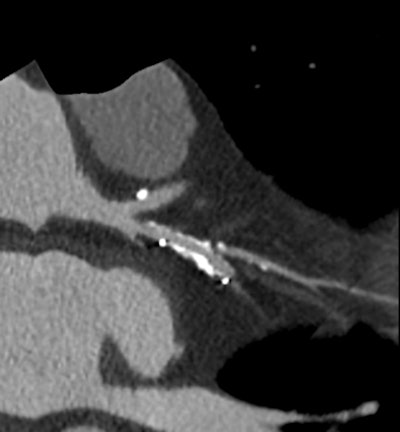

High-definition cardiac CT image obtained on GE Healthcare's Discovery CT750 HD shows bronchial vessels. (Provided by GE)